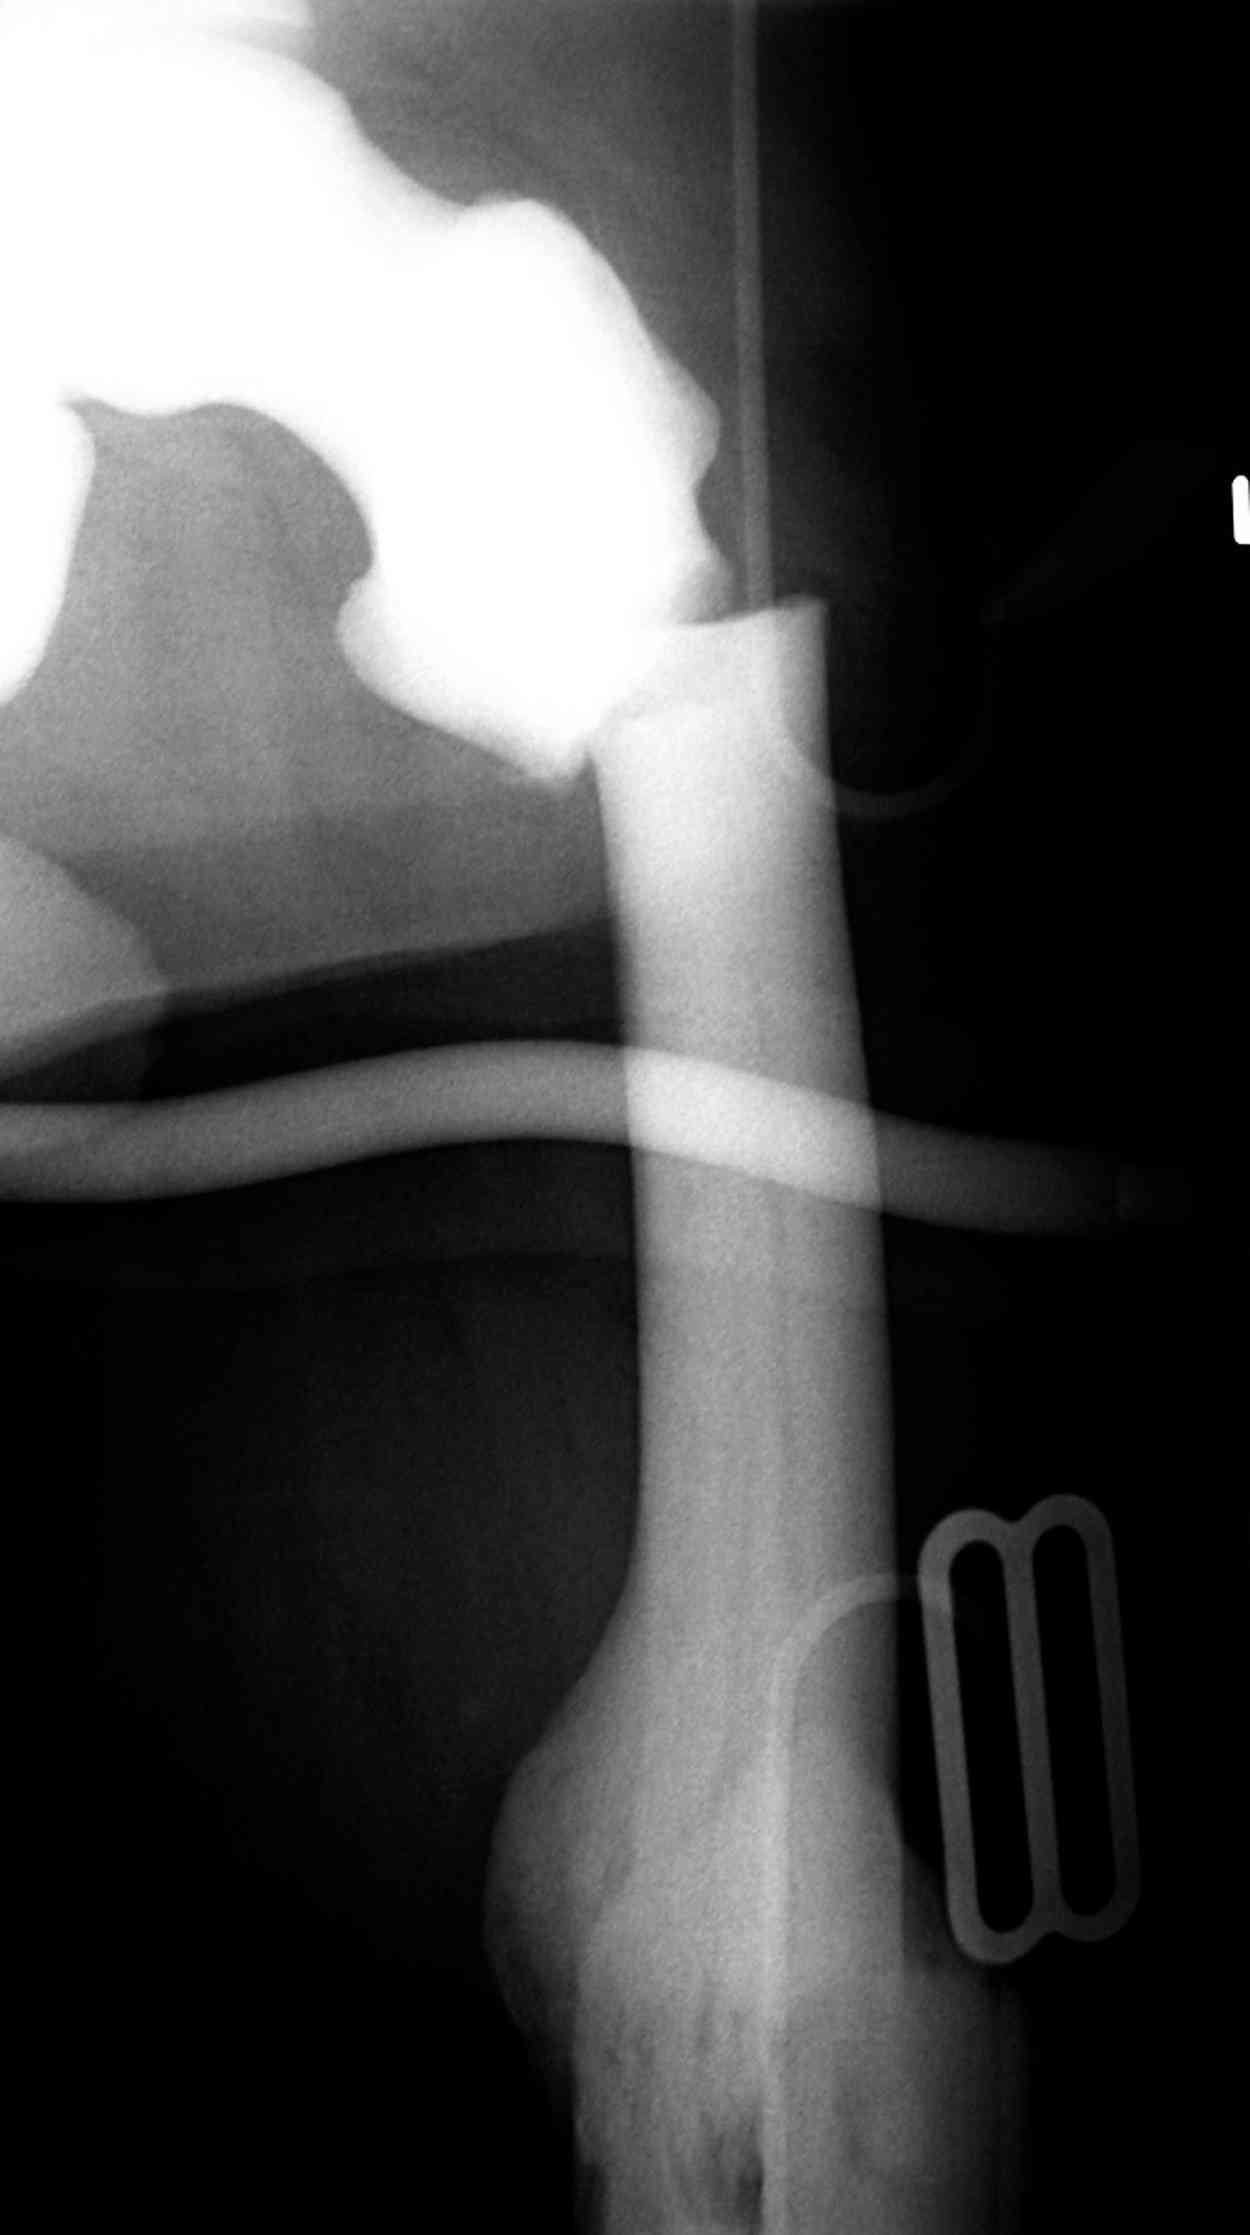

Остеопетроз характеризуется болями в костях, а на ренгене следы множественных несращении длинных трубчатых костей и “белая-мелоподобная” кость.

“При лечении переломов у больных с остеопетрозом (в прошлом году был случай) необходимо быть готовым к длительным операциям из-за трудности

обработки традиционными методами "мраморной" кости, иметь в наличие достаточное количество свежих острых инстументов и персонала при необходимости замены (были случаи отстрочки операции на следующий день из-за физической усталости персонала), и надо избежать особо трудоемких операции как интрамедуллярное сверление”.

Не являюсь специалистом по костной патологии, но мне кажется, на ренгенограмме множественные мета-диафизарные образования напоминяющее змееподобных извилистых линии и периостеальные ламинирование очень напоминяет картину остеонекроза (инфаркта) костей, возможно связано с длительным применением стероидов.

слайды из прошлегодного случая.

Djoldas Kuldjanov, MD

Department of Orthopedic Surgery

St. Louis University Medical Center